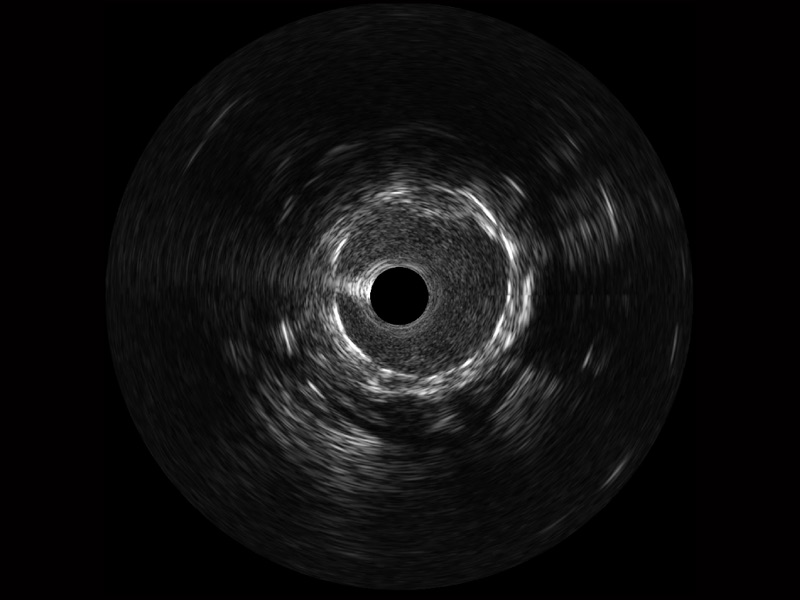

临床图

远场分支血管及导丝

支架内血栓

组织脱垂